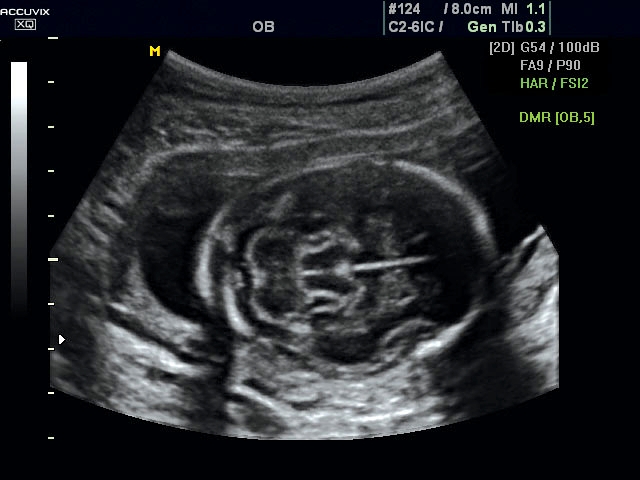

Magzati koponya képe normál 2D módbanMagzati koponya 2D képe bekapcsolt Dynamic MR funkcióvalMagzat törzsének képe normál 2D módbanMagzat törzsének képe bekapcsolt Dynamic MR funkcióvalMagzat felsőajakjának és orrának képeMagzat felsőajakjának és orrának képe bekapcsolt Dynamic MR funkcióval

A DynamicMR alkalmazása az átlagos ultrahang teljesítményt a zaj és szemcsézettség jellegű műtermékek kiszűrése révén a vizuális diagnosztika, a precizitás és a pontosság új szférájába emeli. Figyelje meg a cerebellum, CSP és cisterna magna élstruktúráit, mennyire pontosan definiáltak és a teljes agyi struktúra ábrázolása a Dynamic MR alkalmazásával milyen látványosan javul.